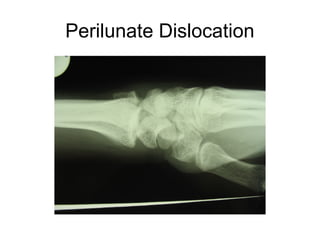

This document discusses several cases of scaphoid fractures in different patients. A 42-year-old female presented with carpal tunnel syndrome and wrist pain after a fall and was found to have a large cyst and fracture in her scaphoid bone. A 16-year-old male reported four months of painful wrist after a skateboarding injury. Imaging also showed a non-union in the wrists of a 42-year-old man bilaterally. Surgical treatment including open reduction and internal fixation with bone grafting was performed in some cases.